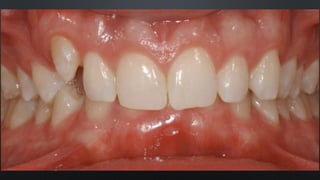

• OVERBITE OU SOBREMORDIDA

RELAÇÃO ENTRE ARCOS

TRESPASSE VERTICAL

• REFERE-SE AO QUANTO OS INCISIVOS SUPERIORES COBREM NOS INFERIORES

• APROXIMADAMENTE 30%

• OVERJET OU SOBRESALIÊNCIA

TRESPASSE HORIZONTAL

• REFERE-SE AO DISTANCIAMENTO ENTRE OS INCISIVOS SUPERIORES E INFERIORES

• NORMALMENTE 2MM

• OVERBITE OUSOBREMORDIDA RELAÇÃO ENTRE ARCOS TRESPASSE VERTICAL • REFERE-SE AO QUANTO OS INCISIVOS SUPERIORES COBREM NOS INFERIORES • APROXIMADAMENTE 30%

• OVERJET OUSOBRESALIÊNCIA RELAÇÃO ENTRE ARCOS TRESPASSE HORIZONTAL • REFERE-SE AO DISTANCIAMENTO ENTRE OS INCISIVOS SUPERIORES E INFERIORES • NORMALMENTE 2MM